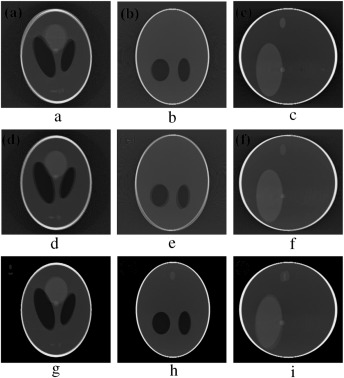

and three rotational (roll, pitch, yaw ) parameters of motion, we simulated several abrupt and gradual variations of motion on the 3D Shepp–Logan phantom. The cone-beam parameters listed in  Table 2  are used for our simulation. For abrupt variation of motion, we perturbed the 3D Shepp–Logan phantom with three different types of motion (translational, rotational, and rotational & translational combined) in three different test cases. Some of the images of motion corrupted projections and the axial, coronal and sagittal slices of the reconstructed volume of the above cases are plotted in  Figure 7 , Figure 8  and Figure 9 . For gradual variation of motion, we varied each parameter of motion separately in six different test cases. For gradual translational motion corruption cases, we gave ±6 mm of perturbation with a step size of ±1 mm. For gradual rotational motion corruption cases, we gave perturbation of ±5° with a step size of ±1°. The axial, coronal and sagittal slices of the gradual motion corrupted cases (+ perturbation only) are plotted in  Figure 10a  and Figure 10b .  Figure 10a  and Figure 10b  show the motion artifacts created in the reconstructed image due to the gradual perturbation given to the 3D Shepp–Logan phantom during data acquisition time. In Figure 10a , the 1st row shows the artifacts occurred due to the perturbation of +6 mm with a step size of +1 mm along the Failed to parse (MathML with SVG or PNG fallback (recommended for modern browsers and accessibility tools): Invalid response ("Math extension cannot connect to Restbase.") from server "https://mathoid.scipedia.com/localhost/v1/":): {\textstyle X}

-axis given. The 2nd and 3rd rows show the artifacts created due to the similar perturbation given to the phantom along the Failed to parse (MathML with SVG or PNG fallback (recommended for modern browsers and accessibility tools): Invalid response ("Math extension cannot connect to Restbase.") from server "https://mathoid.scipedia.com/localhost/v1/":): {\textstyle Y}

and Failed to parse (MathML with SVG or PNG fallback (recommended for modern browsers and accessibility tools): Invalid response ("Math extension cannot connect to Restbase.") from server "https://mathoid.scipedia.com/localhost/v1/":): {\textstyle Z}

axes, respectively. In Figure 10b , the 1st row shows the motion artifacts (artifacts dominant in the axial slice) occurred due to the rotational perturbation of 5° (clock-wise) with a step size of 1° given about the Failed to parse (MathML with SVG or PNG fallback (recommended for modern browsers and accessibility tools): Invalid response ("Math extension cannot connect to Restbase.") from server "https://mathoid.scipedia.com/localhost/v1/":): {\textstyle Z}

-axis (yaw). The 2nd row shows the motion artifacts (artifacts dominant in the sagittal slice) occurred due to the same rotational perturbation about the Failed to parse (MathML with SVG or PNG fallback (recommended for modern browsers and accessibility tools): Invalid response ("Math extension cannot connect to Restbase.") from server "https://mathoid.scipedia.com/localhost/v1/":): {\textstyle Y}

-axis (pitch). The 3rd row shows the artifacts (artifacts dominant in the coronal slice) occurred due to the rotational variation of similar motion about the Failed to parse (MathML with SVG or PNG fallback (recommended for modern browsers and accessibility tools): Invalid response ("Math extension cannot connect to Restbase.") from server "https://mathoid.scipedia.com/localhost/v1/":): {\textstyle X}

-axis (roll). From  Figure 7 , Figure 8 , Figure 9 , Figure 10a  and Figure 10b , it can be observed that head motion during data acquisition time resulted in doubling, ghosting, blurring and loss of resolution artifacts in the reconstructed images.

Motion artifacts occurred due to translational varaiation of gradual motion.

Figure 10a.

Motion artifacts occurred due to rotational varaiation of gradual motion.

Figure 10b.